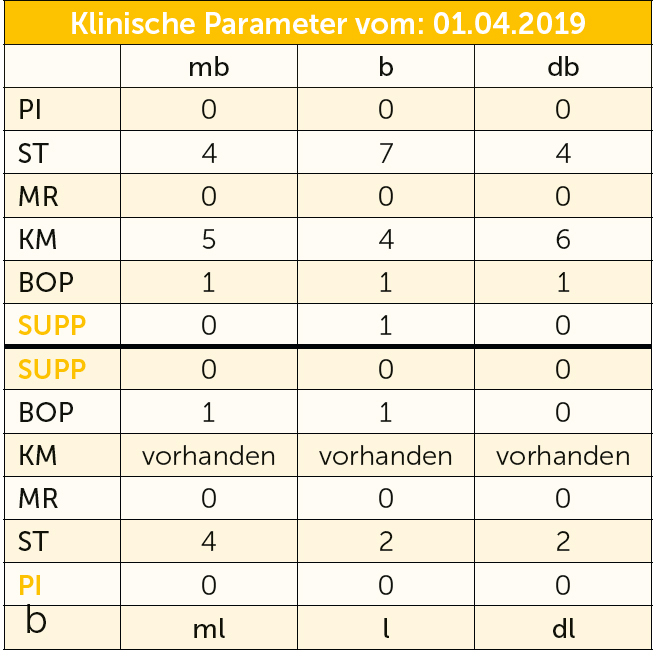

Abb. 3a bis h Falldokumentation mit Zustand nach Implantation und lateraler Augmentation alio loco: a) klinische Ausgangssituation mit Fistelung vestibulär in der Region 12; b) klinische Parameter (PI=Plaque Index 1-3, ST=Sondierungstiefe, MR=Mukosarezession, KM=keratinisierte Mukosa, BOP=Bleeding on probing, SUPP=Suppuration); c) radiologische Ausgangssituation mit initialem periimplantären Knochenabbau; d) operativer Zugang; e) Defektdarstellung nach Entfernung des periimplantären Entzündungsgewebes; f) Defektaugmentation mit einem Gemisch aus Eigenknochen und xenogenem Knochenersatzmaterial; g) Kollagenmembran; h) das aus dem Gaumenbereich entnommene Bindegewebstransplantat (BGT).

Abb. 3i bis m Falldokumentation mit Zustand nach Implantation und lateraler Augmentation alio loco: i) okklusale Ansicht mit eingebrachtem BGT vestibulär in der Region 12; j) Wundverschluss mit Naht; k) klinische Situation 9 Monate post operativ; l) okklusale Ansicht; m) klinische Parameter.